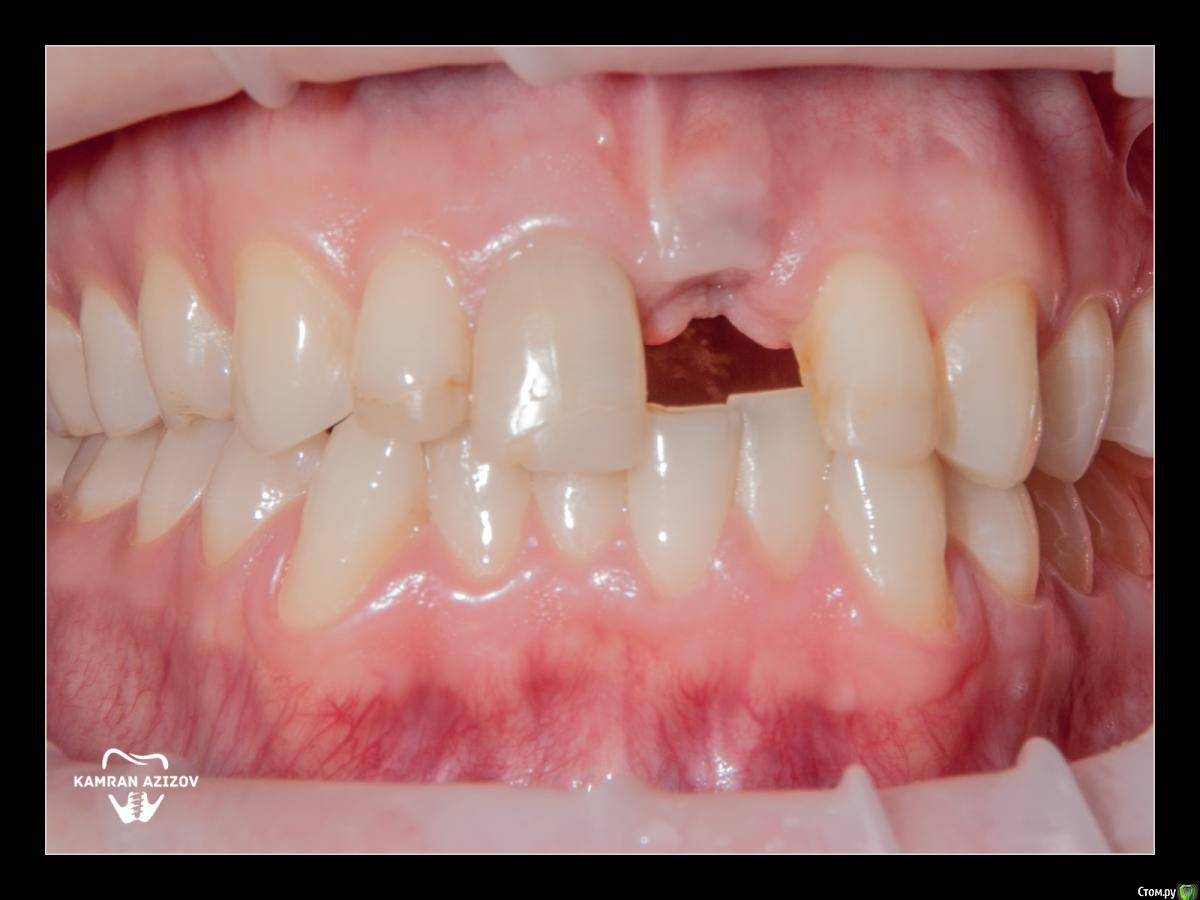

kamranchick Опубликовано 8 октября, 2019 Поделиться Опубликовано 8 октября, 2019 удаление зуба+консервация лунки с вестибулярным ССТчерез 2 месяца имплантация с фдм по карлоссучерез 4 месяца замена на более длинный фдм и широкийпостоянная коронка 5 Ссылка на комментарий

Irouil Опубликовано 9 октября, 2019 Поделиться Опубликовано 9 октября, 2019 Жаль фотки до удаления нет, кажется там дефект вестибулярно был Ссылка на комментарий